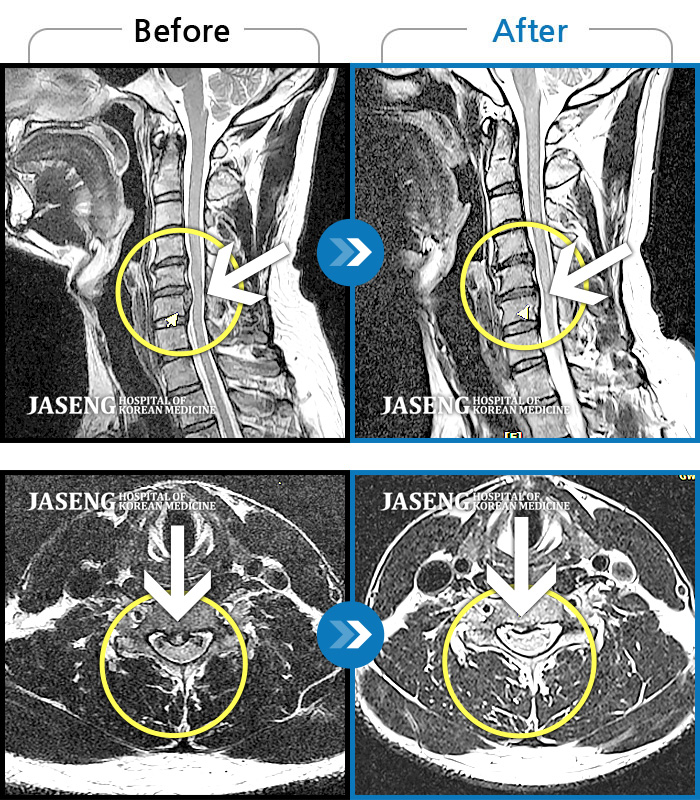

자생 비수술 한방통합치료 후

터진디스크가 흡수된 모습

Before

After

비수술 치료만으로

터진 디스크 흡수

좌측 승모근부터 견갑골까지 이어지는 통증, 좌측 상완 비증으로 내원하셨습니다.

2024.04.03 ~ 2024.10.24